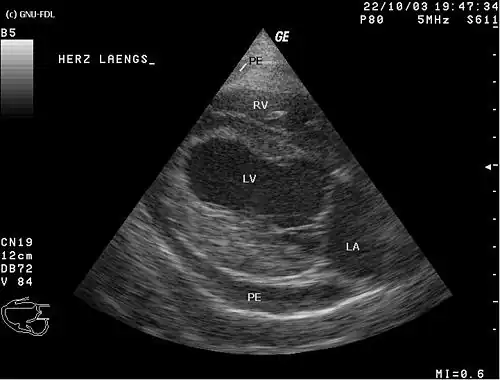

Serce jest umieszczone w worku osierdziowym, w którym w warunkach fizjologicznych jest bardzo mała ilość płynu surowiczego.

Między wewnętrzną blaszką trzewną osierdzia, pokrywającą mięsień sercowy, a zewnętrzną blaszką ścienną występuje wąska szczelina – jama osierdzia, wypełniona płynem surowiczym (zwilża on blaszki osierdzia, ocierające się o siebie w czasie pracy serca). Zapalenie osierdzia ostre lub przewlekłe przebiega zwykle z wysiękiem, niekiedy (zapalenie osierdzia zaciskające) z powstawaniem grubych zrostów i powstawaniem tzw. serca opancerzonego, upośledzającego znacznie jego czynność; przyczyną są m.in. zakażenia, rzuty choroby reumatycznej, gruźlica.

Osierdzie składa się z dwóch części – osierdzia surowiczego i osierdzia włóknistego. Pomiędzy blaszką trzewną i ścienną osierdzia surowiczego znajduje się jama osierdzia zawierającą niewielką ilość płynu surowiczego[2].